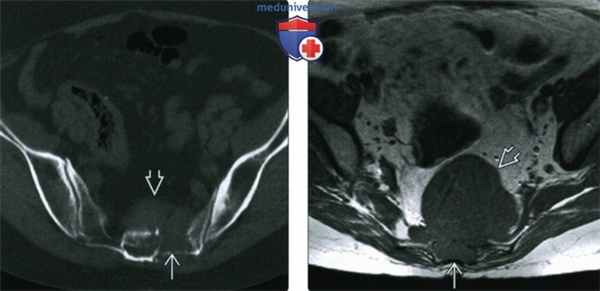

(Слева) КТ, аксиальная проекция, без контрастного усиления: литический костный очаг в левом крыле крестца и превертебральный мягкотканный компонент, распространяющийся из костного очага. Опухоль имеет типичные для хордомы расположение и лучевые признаки. Схожими признаками могут обладать и другие новообразования, такие, как: нейрофиброма, хондросаркома и гигантоклеточная опухоль.

(Справа) МРТ, аксиальная проекция, режим T1: у этого же пациента визуализируется костный очаг и мягкотканный компонент, характеризующиеся однородным сигналом низкой интенсивности, изоинтенсивным по отношению к скелетной мышце. Новообразование смещает кишечник кпереди.